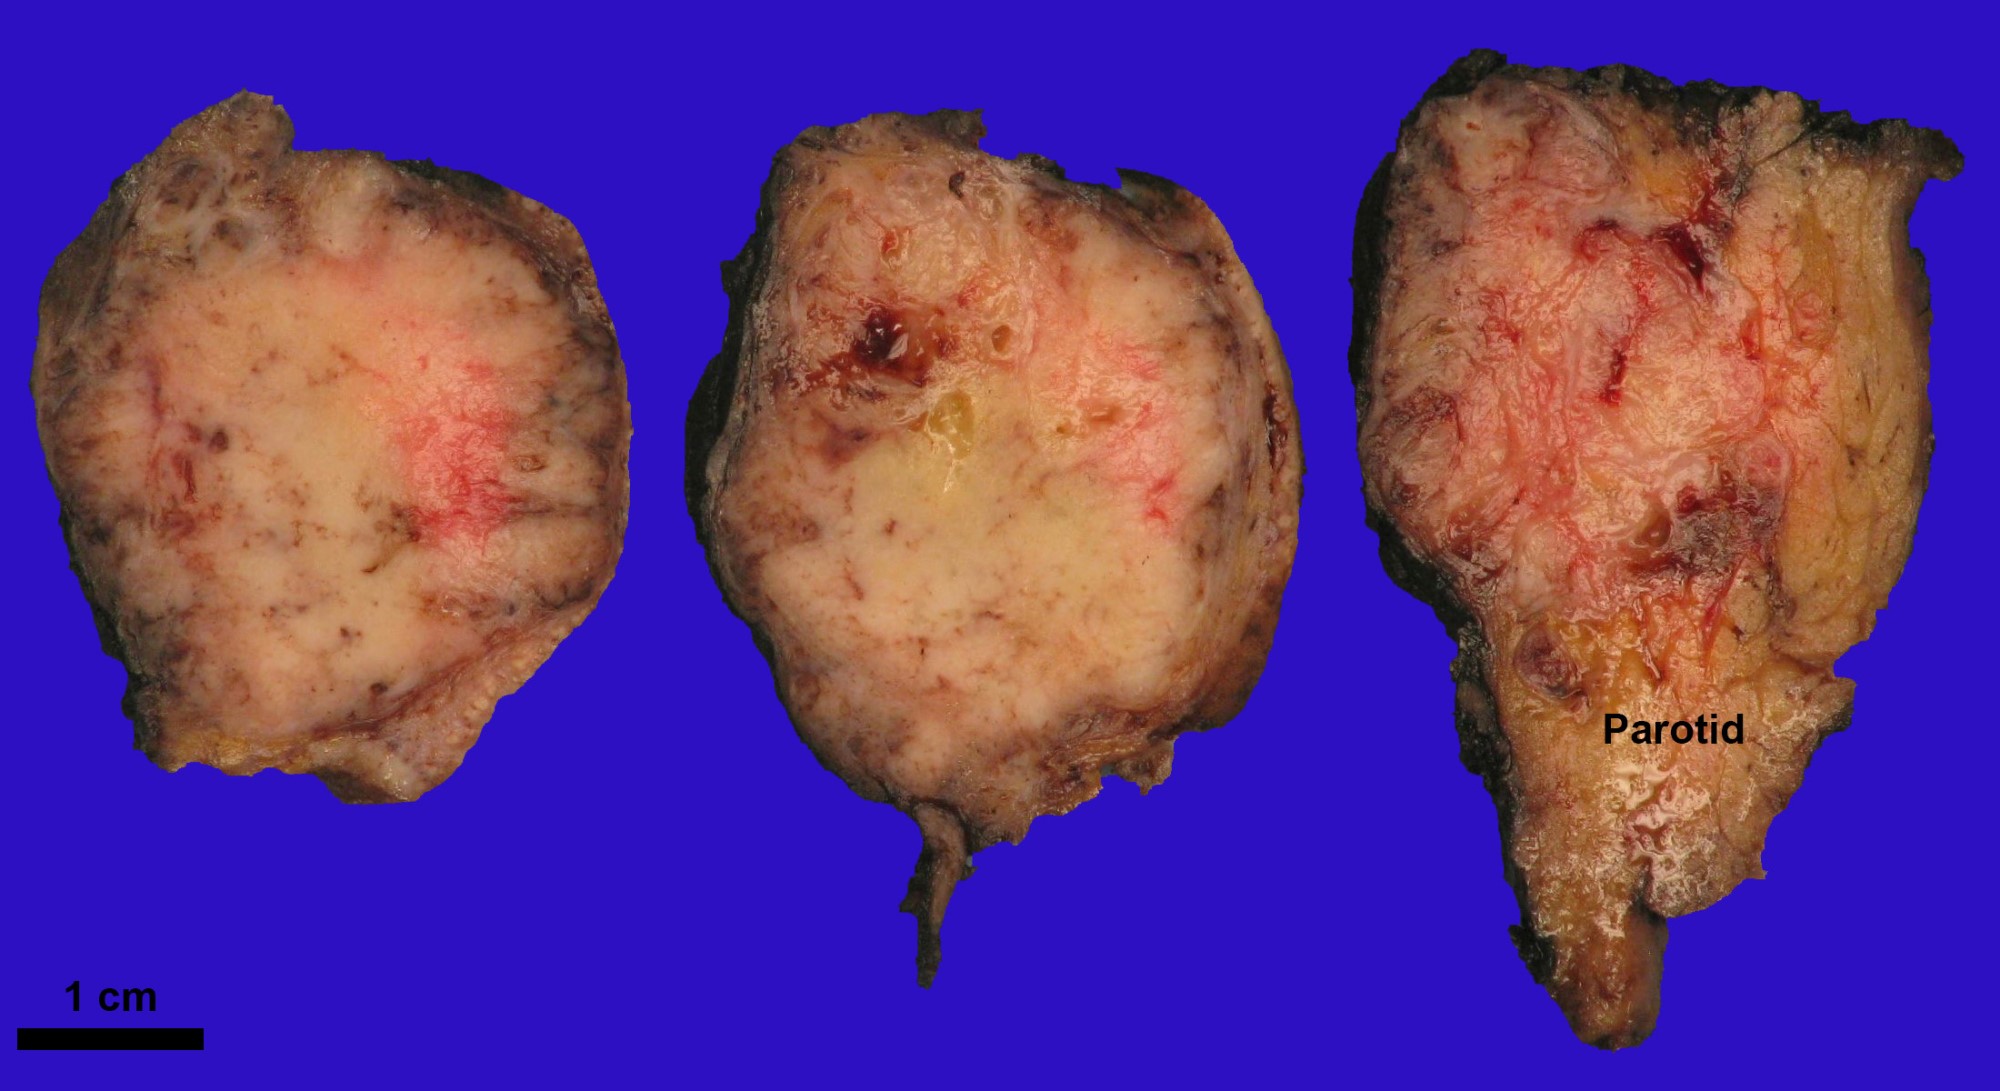

Gross description

- Gross appearance is nonspecific

- Tumor is often present as an expansile, lobulated to multinodular, beige to white mass, sometimes with ill defined / infiltrative border

Contributed by Abeer Salama, M.D. and Bin Xu, M.D., Ph.D.